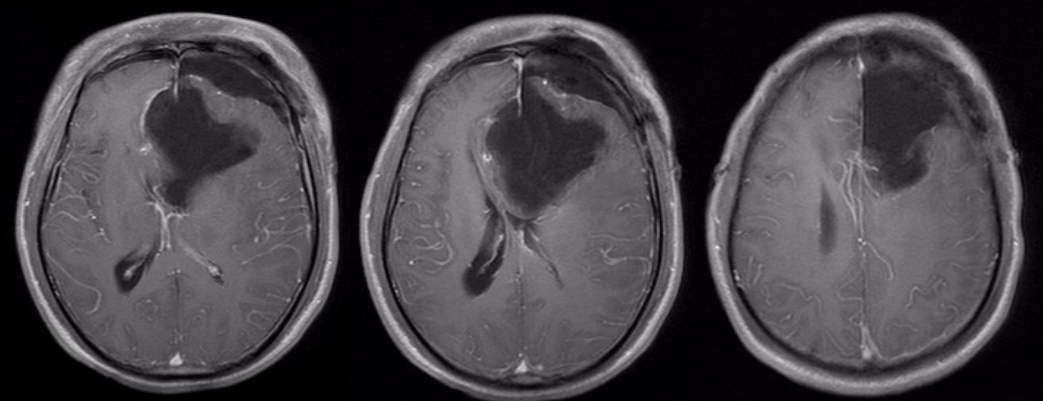

术后半年MRI增强